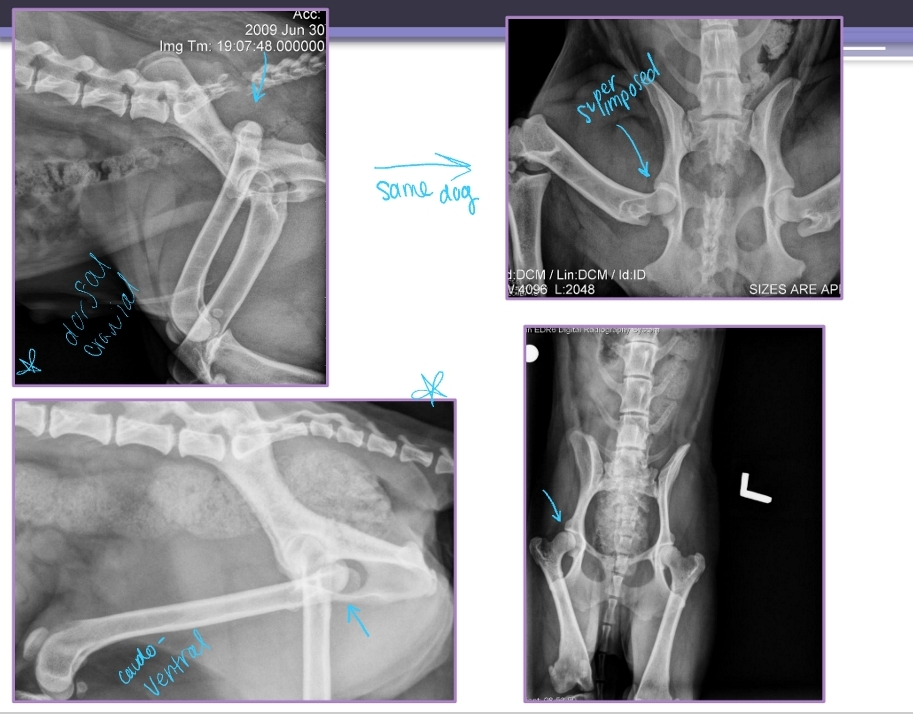

Shoulder Luxation

Et: congenital or trama

Ligamentous laxity, Glenoid dysplasia

Sig: Young small breeds (congenital)

Cs: lameness

Tx:

Congenital: MCL repair, arthroplasty

Acquired: Medial, Closed reduction, Bandage 2 weeks, rest 2 weeks, sling, MCL repair

Velpeau sling: for medial luxation

Neutral sling: for lateral luxation

Salvage: Arthrodesis, Glenoid excision

Elbow Luxation

Et: Traumatic most common

Traumatic: Radius and ulna luxate laterally

large medial condyle of humerus prevents medial luxation

Congenital: abnormally shaped radius/ulna/ humerus

Cs: Unable to bear weight, Forelimb abducted and externally rotated (elbow out, paw rotated in)

Dt: limb resists extension, prominent radial head, PAINFUL, Radiographs AP views!

Acquired: Closed reduction under GA + brachial plexus block

Flex elbow to 100° and internally rotate

Extend elbow slightly, adduct and inwardly rotate antebrachium while applying medial pressure on radial head

Immobilize 2 weeks w/ spica split

Congenital

If reducible → place transarticular pin while still growing!! remove later on

If non-reducible → arthrodesis when older in standing position

Hip Luxation Pathophysiology

Et: Results from failure or tear of Joint capsule or Round ligament

Most common joint luxation in dogs

Types:

Craniodorsal (#1): hit-by-car or blunt trauma

Caudoventral: fall with abduction

Hip Luxation Treatment

Closed Reduction:

Craniodorsal luxation:

External rotation → Pull limb caudally and distally → Internal rotation

Ehmer sling 2w → Maintain abduction + internal rotation

Caudoventral luxation:

Abduct limb → Provide distraction → Apply lateral and proximal pressure

Hobbles 2w → Maintain adduction

Open Reduction and Fixation:

Why: Closed reduction unsuccessful

How: Toggle pin technique

Creates synthetic round ligament

Hip must have no evidence of OA

Salvage:

Why: Chronic luxation’s, Damaged articular cartilage, OA

How: Total hip replacement or Femoral head and neck ostectomy(FHNO) more common(cheaper)